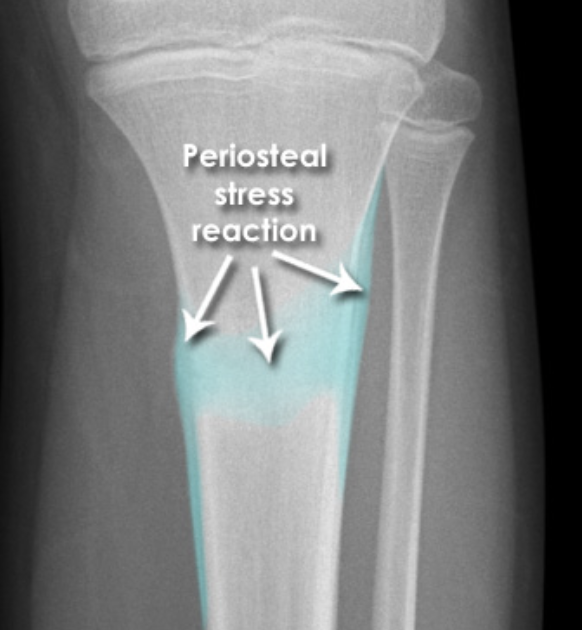

What type of fracture is depicted [1]

Tibial stress fracture

* Periosteal stress reaction are signs of stress injury (often not present on the initial X-ray)

* History of chronic pain worsened by activity